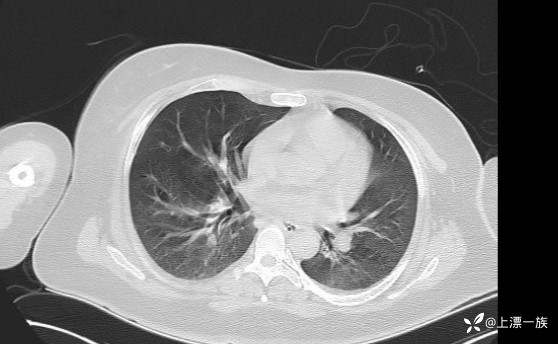

当天胸部CT